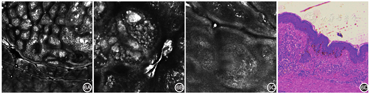

RCM特征:①表皮处,棘层可见角质形成细胞排列整齐,呈蜂窝状,伴明亮的鹅卵石样结构聚集,对应于组织病理中大量色素颗粒沉着;亦可见表皮结构紊乱,蜂窝状结构消失,出现Paget样细胞。与黑色素瘤相比较,Paget样细胞比例较少,且多为灶性分布的高亮度梭形或树突细胞。在无色素型皮损中,可见低亮度Paget样细胞(图3A)[11];②在真表皮交界处乳头间隙增宽,呈现网筛状结构(图3E)[12];③真皮层可见高折光团块样聚集,界限通常较清晰(图3C)[13]。

本组图片引自文献[11],已获出版商授权